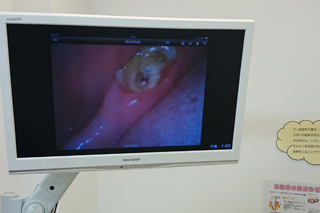

口腔内カメラ

当院では患者様により細かく口の中の状態を確認してもらうため、口腔内カメラを用いた説明を行っております。

通常鏡などでは見られない部位でも、口腔内カメラを使い大きく鮮明なモニターでしっかりとご確認して頂く事が可能です。